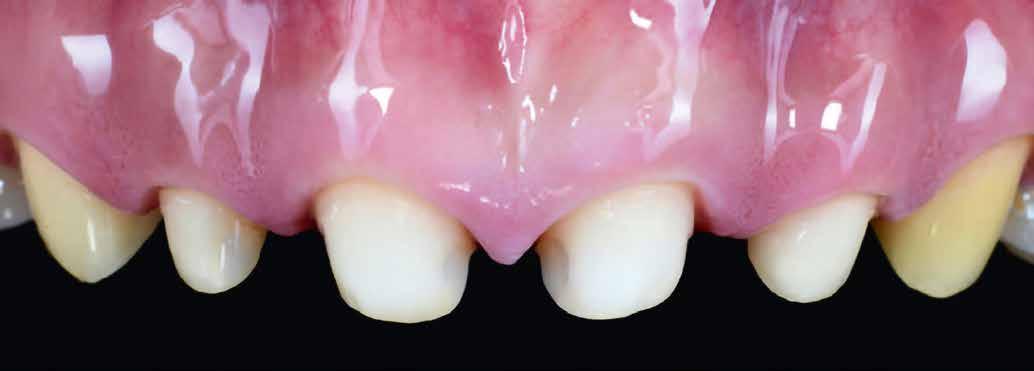

építményhez gyári Camlog titánbázist használtunk, amit előzetesen befedtünk DCMhotbond fusio connect spray-vel. A titánbázis felületi kondicionálásához alkalmazott anyag kiváló, résmentes és tartós kötési alapot teremt a bázis és a rá készülő cirkon konstrukció között1. A cirkónium-dioxid egyedi felépítmény tervezését primer teleszkóp koronaként választottuk ki a CAD-szoftveres lehetőségek tárából. A felső mintát a beszórt titánbázissal ínymaszkkal és anélkül is beszkenneltük, akárcsak az antagonista mintát. A titánbázist hárompontos vonatkoztatással illesztettük a digitális mintába, majd megállapítottuk a behelyezési irányt és az illesztő paramétereket (7–13. képek).

Tervezés és kivitelezés a laboratóriumban

Az implantátumról készült lenyomat, valamint az alginát antagonista fertőtlenítése után szuperkemény gipszből az előírások szerint elkészültek a minták. A felső mintát a technikai implantátum körül levehető ínymaszkkal készítettük. SAM-arcív segítségével habituális okklúzióba helyeztük a mintákat. A felső mintát előkészítettük a digitális tervezéshez, enyhén megformáltuk az emergenciaprofilt, hogy tökéletes legyen a rózsa-fehér esztétika. A fogszínt – a pácienssel történt egyeztetést követően – dokumentáltuk.

A mintát beolvastuk (D1000, 3Shape), majd megterveztük a munkát (3Shape Dental System) (6. kép). A fel -